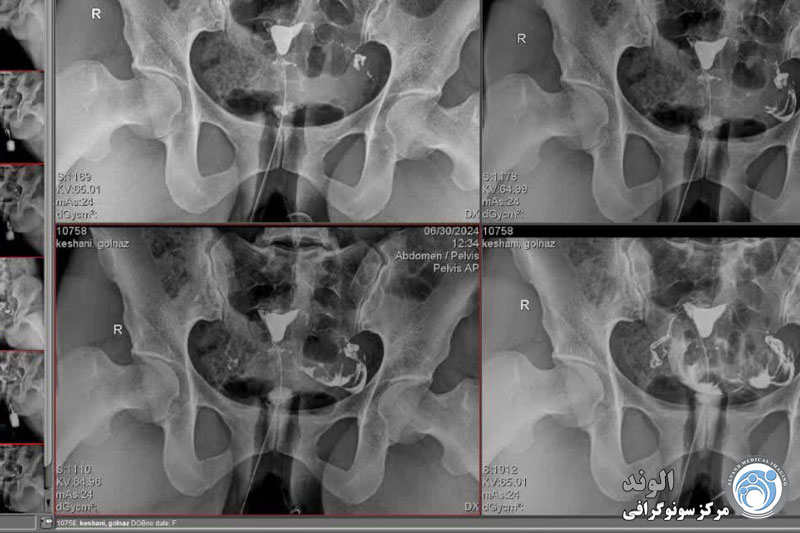

بیمار در وضعیت زنان (به پشت خوابیده، زانوهای خم شده و از هم باز)، زیر دستگاه اشعه ایکس قرار می گیرد. پزشک یک اسپکولوم را وارد واژن میکند، سپس یک کانولا را در دهانه رحم قرار میدهد که از طریق آن یک ماده حاجب تزریق میکند. این به داخل رحم و لوله های فالوپ گسترش می یابد. اشعه ایکس برای مشاهده پیشرفت خوب محصول و تجسم اندام ها گرفته می شود.

هیستروسالپنگوگرافی توسط رادیولوژیست انجام می شود. معاینه بدون بیهوشی انجام می شود. بیمار در موقعیت "زنان و زایمان" مستقر می شود. پزشک اسپکولوم را قرار می دهد، دهانه رحم را ضد عفونی می کند و سپس یک پروب را با روش طبیعی وارد رحم می کند. او به تدریج ماده حاجب را تزریق می کند. به طور معمول، ماده حاجب به تدریج رحم و لوله های فالوپ را کدر می کند تا زمانی که به حفره صفاقی منتقل شود.

چندین عکس رنگی رحم قبل، حین و بعد از تزریق محصول گرفته می شود و این در موقعیت های مختلف:

اشعه ایکس بدون آماده سازی (جستجو برای کلسیفیکاسیون لگن)؛

اشعه ایکس پر شدن ضعیف (پولیپ ها یا فیبروم های زیر مخاطی را برجسته می کند).

اشعه ایکس پر شدن لوله (ارزیابی وضعیت مخاط لوله).

عکس پروفایل (ارزیابی موقعیت رحم و مسیر لوله های فالوپ)؛

اشعه ایکس دیررس (بررسی گردش خون صفاقی، جستجو برای چسبندگی لگن).

در اصل، HSG یک ارزیابی رادیوگرافی از حفره رحم و لوله های فالوپ با استفاده از فلوروسکوپی سرپایی بلادرنگ با تزریق ماده حاجب رادیویی مات از طریق کانال دهانه رحم را نشان می دهد. کانال دهانه رحم، کانتور حفره رحم و لومینای رحم و لوله شامل بخش های قرنیه، ایستمی و آمپولری و تعیین

ابتدا یک اشعه ایکس اولیه گرفته می شود. پس از تزریق رنگ، چهار عکس با اشعه ایکس زمانبندیشده دیگر برای ارزیابی کانتور پوشش آندومتر حفره رحم، لولهها و باز بودن لولهها گرفته میشود. اگر لوله ها باز باشند، اجازه می دهند رنگ در انتهای تخمدان به داخل حفره صفاقی بریزد. هیستروسالپنگوگرافی در اکثر بیماران یک روش بی خطر است، اما خطراتی دارد که خوشبختانه نادر است.